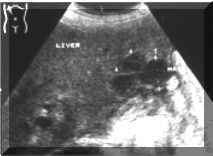

Metastatic

disease

is

multifocal

in

approximately

90

percent

of

patients

(Picture1).

Picture1.

Multiple,

small

metastases.